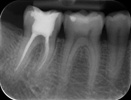

Viele Zahn- und Gewebeschäden im Mund beginnen im Verborgenen. Besonders die Zahnzwischenräume und jene Bereiche der Zähne und des Knochens, die vom Zahnfleisch bedeckt sind, können von blossem Auge nur ungenügend beurteilt werden. Röntgenaufnahmen helfen, vorhandene Schäden rechtzeitig zu entdecken.

Die Zahnröntgenaufnahme ist deshalb ein unverzichtbares Mittel zur Diagnoserstellung und zur Planung einer Behandlung. Sie stellt zudem ein wichtiges zahnmedizinisches Dokument dar.

Beim Röntgen werden elektromagnetische Wellen von hoher Energie (Photonen) durch das zu untersuchende Gewebe oder Organ auf einen Film oder Sensor gestrahlt. Aufgrund der unterschiedlichen Dichte der verschiedenen Körpergewebe (Haut, Schleimhaut, Knochen, Zähne) erreichen mehr oder weniger Photonen den Film oder Sensor und stellen dadurch die Gewebestrukturen in unterschiedlichen Grautönen dar.

Vom einfachen Einzelzahnröntgenbild bis zu computerunterstützten dreidimensionalen Schichtaufnahmen der Zähne und des Kiefers gibt es eine Vielzahl unterschiedlicher Aufnahmetechniken.